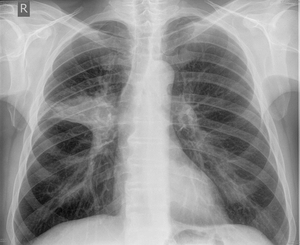

Рентгенография органов грудной полости